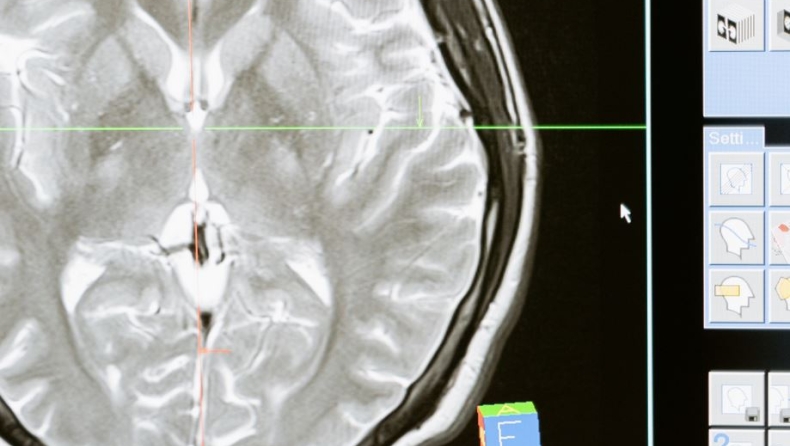

Κάνε το τεστ και βρες την ηλικία που έχει ο εγκέφαλος σου

Το σώμα γερνά, όμως οι πνευματικές μας ικανότητες πως υπολογίζονται;